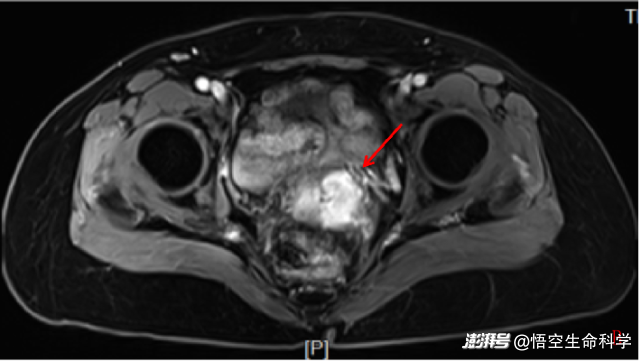

回輸一個(gè)月后,宮頸腫物較前稍增大